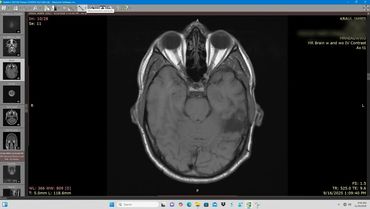

Axial MRI scan showing detailed brain structures including eye sockets and brain tissue.